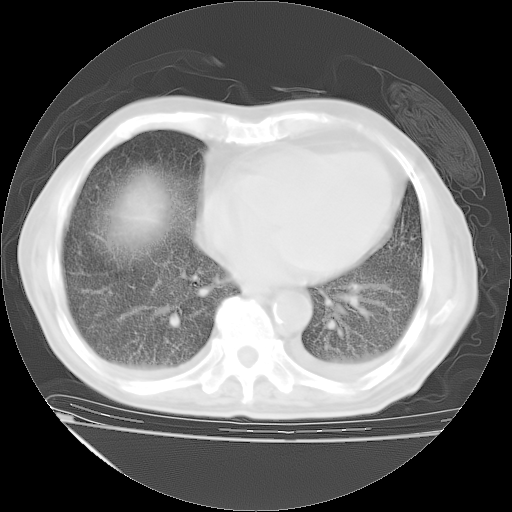

甲强龙80mg/日+抗结核治疗(异烟肼+利福霉素+乙胺丁醇)10天。复查肺部CT。

治疗10天肺部CT

补充下:5月9日胸部CT:似乎已见双下肺胸腔积液了,鉴于目前有下肢水肿,肝功示:白蛋白低,应注意多浆膜腔积液(漏出液可能大?),需注意!